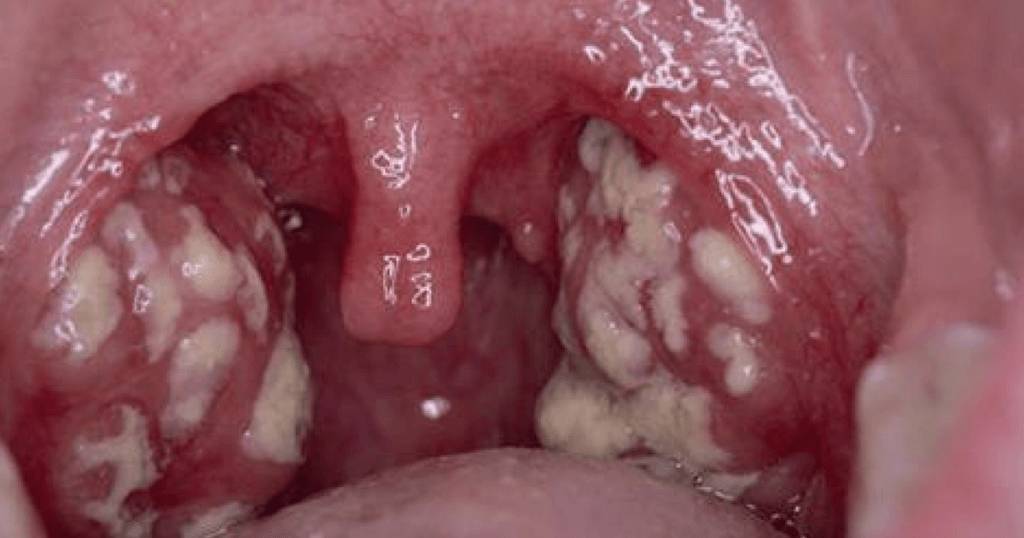

На фото лакунарная ангина. На отечных и покрасневших миндалинах видны беловатые островки гноя

При лакунарной ангине гнойное воспаление сначала развивается в углублениях миндалин (лакунах), а затем переходит на их поверхность. Признаки схожи с проявлениями фолликулярной формы, но протекание более тяжелое.

В лакунах скапливается гнойный экссудат, слизистая миндалин краснеет и отекает, на ее поверхности заметны отдельные участки желтовато-белого налета. Они легко снимаются, после чего снова появляются на том же месте, могут сливаться, полностью покрывая миндалины.